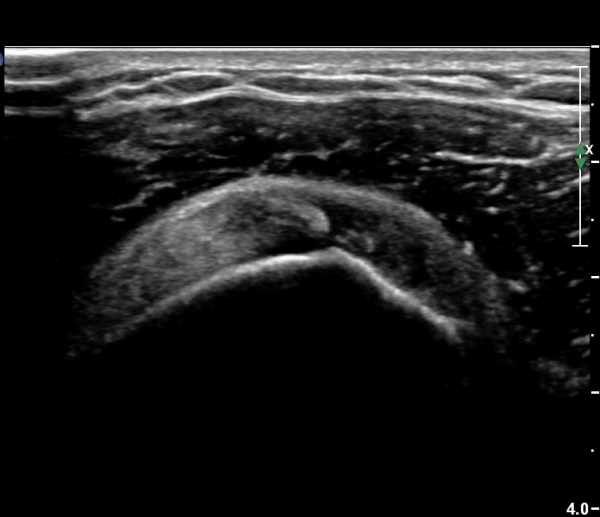

¿À±¸µ¹±â°ßºÀÀδë Á¾´Ü¸é°Ë»ç¿¡¼­ Àδ밡 Á¤»óÀûÀ¸·Î °üÂûµÇ°í(»çÁø 4)

°ßºÀ¿¡ À§Ä¡ÇÑ  ŽÃËÀÚ¸¦ ¾à°£ ¸»´Ü(caudal)À¸·Î À̵¿ÇÏ´Ï °ßºÀ ¾Æ·¡Ãø¿¡¼­ ³»ÃøÀ¸·Î °í¿¡ÄÚ ¼®È¸È­À½¿µÀÌ °üÂûµÈ´Ù(»çÁø 5).